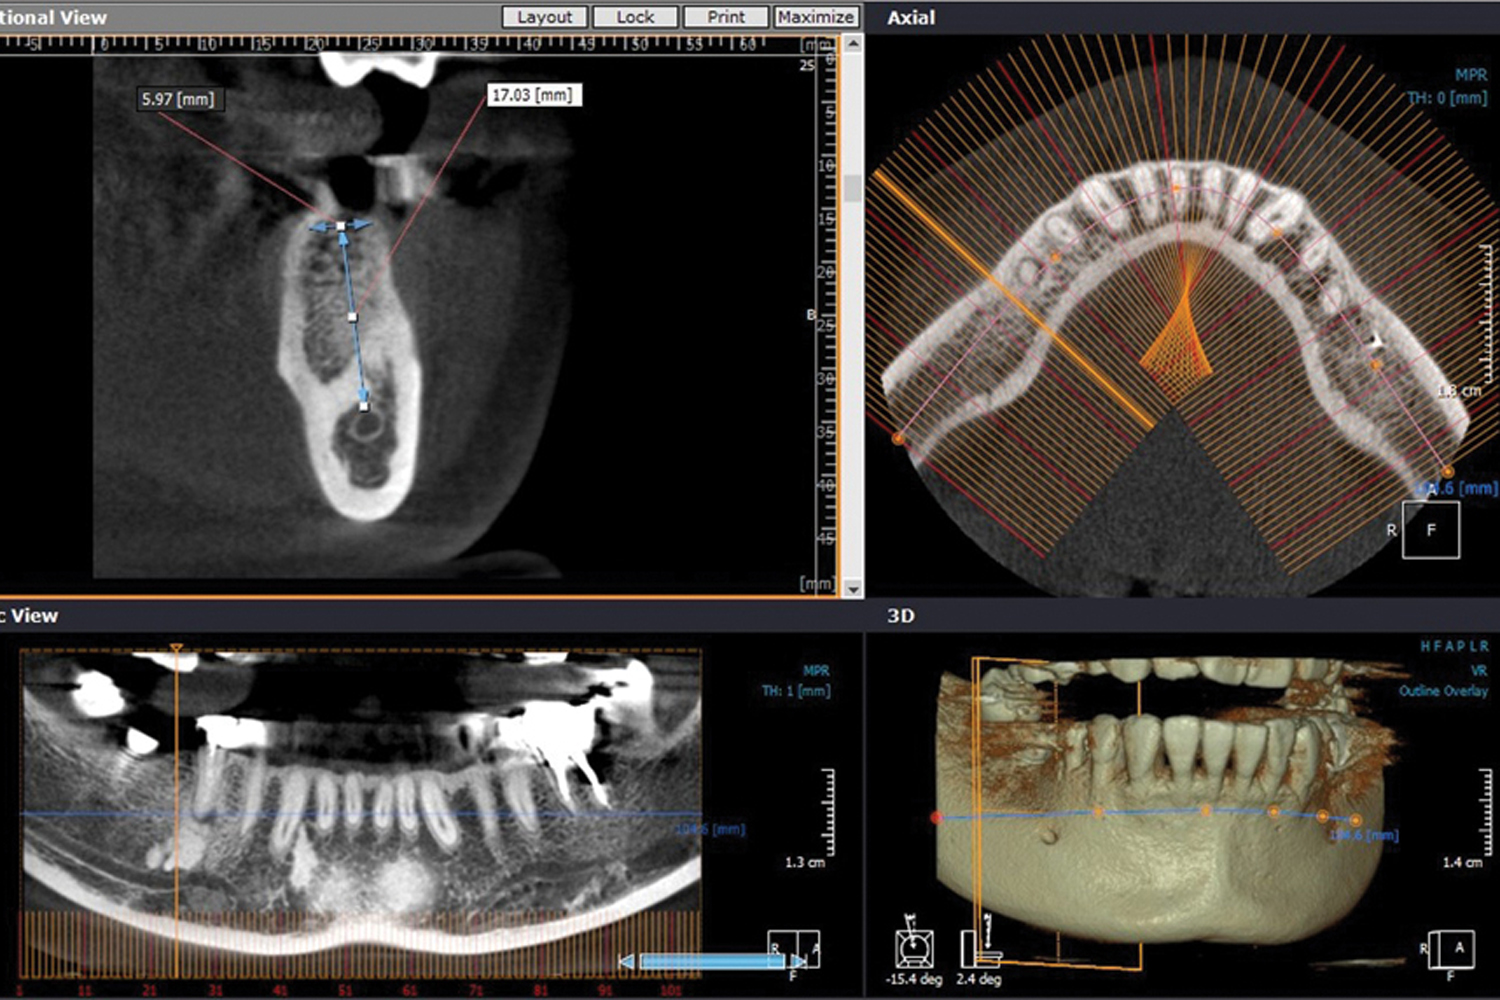

Advanced Dental Diagnostics & 3D CBCT X-Ray

Lilladent offers advanced dental diagnostics including CBCT 3D X-rays, panoramic and intraoral X-rays for accurate diagnosis, implant planning, and safe dental treatment.

Dental implant - Full mouth rehabilitation

At Lilladent, we offer safe, effective, and minimally invasive dental implantation with a focus on precision and comfort. Using advanced technology like CBCT, surgical guide and 3D intraoral scanner, we ensure accurate placement and custom crowns for a perfect fit. We recommend early implant placement after extraction to avoid bone grafting, and use osseo-condensation technique to reduce the need for sinus lifts, speeding up recovery. For patients needing quicker results, immediate implant placement is available.